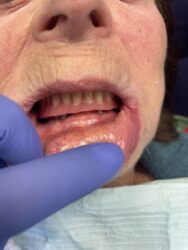

I have a question about restoring this case. The plan was to do over denture. But now the patient can’t handle the denture and she wants a bridge. Implants are fully healed and ready to be restored. She doesn’t want to wait another 5 months ( so adding 2 posterior implants is not an option). How would you go about restoring this? Screw…

Read more

• I typically try not to cantilever more than one tooth. In this case you may be able to get away with two smaller teeth and get to the 2 pre molar if placing more posterior implants aren’t an option.